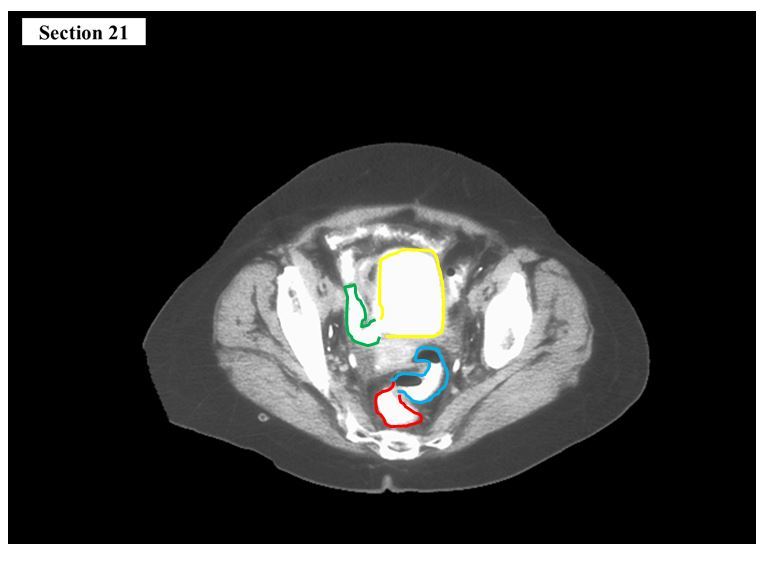

The yellow structure is the ___

The red cavity is the ___

A

urethra

anal canal